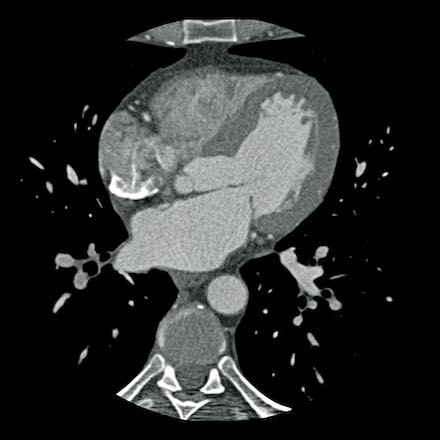

case 1 – CAD-RADS 2/P1

First, scroll through the scan.

Not all images are included. Some images without any abnormalities are skipped

from the series.

How would you describe the findings on the coronary CTA?

The findings are:

- Agatston score of

this patient was 14 (P1). Please, also note the calcification of the aortic valve. - Some partially

calcified and calcified plaques are present in the LAD with mild stenosis

(25-49%). - Calcified-plaque in

the LCX causing minimal stenosis (<25%). - Non-calcified

plaque in the distal RCA causing minimal stenosis (<25%). - This patient classifies

as CAD-RADS 2/P1, which means no further workup is needed.